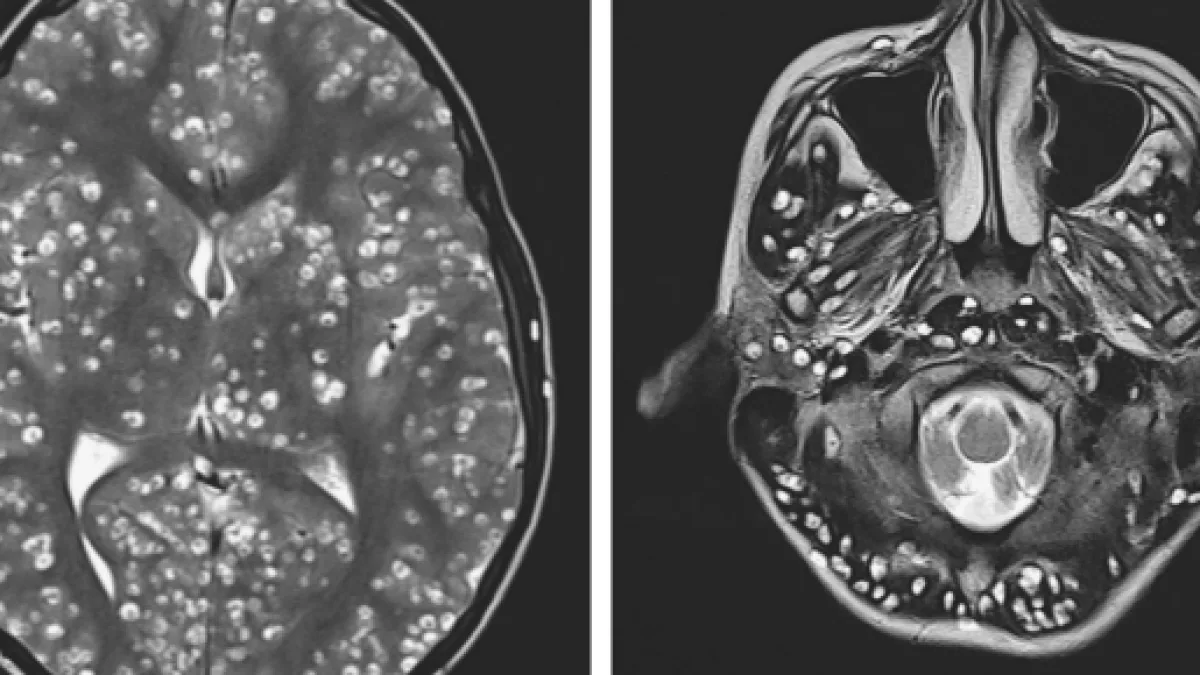

Só após a ressonância magnética que os médicos identificaram o problema e puderam observar os estragos causos em decorrência dos cistos no córtex e tronco cerebral do paciente.

Os médicos encontraram também cistos no olho direito. Em decorrência da localização dos cistos, os médios optaram por não tratar o jovem com antiparasitários, que poderiam acarretar em sangramentos cerebrais mais graves o que resultaria na perda da visão do paciente. Dessa forma, o rapaz recebeu o medicamento dexametasona e antiepiléticos. Mesmo com os esforços da equipe médica, o jovem morreu duas semanas depois de ter chegado ao hospital.